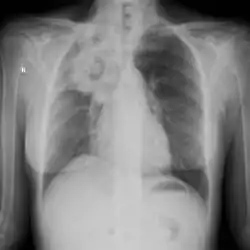

The extent of infection may be seen on X-ray or CT scan. On chest X-ray and CT, pulmonary aspergillosis classically manifests as a halo sign, and later, an air crescent sign.[21]

Chest X-ray: mass overlying the left hilum